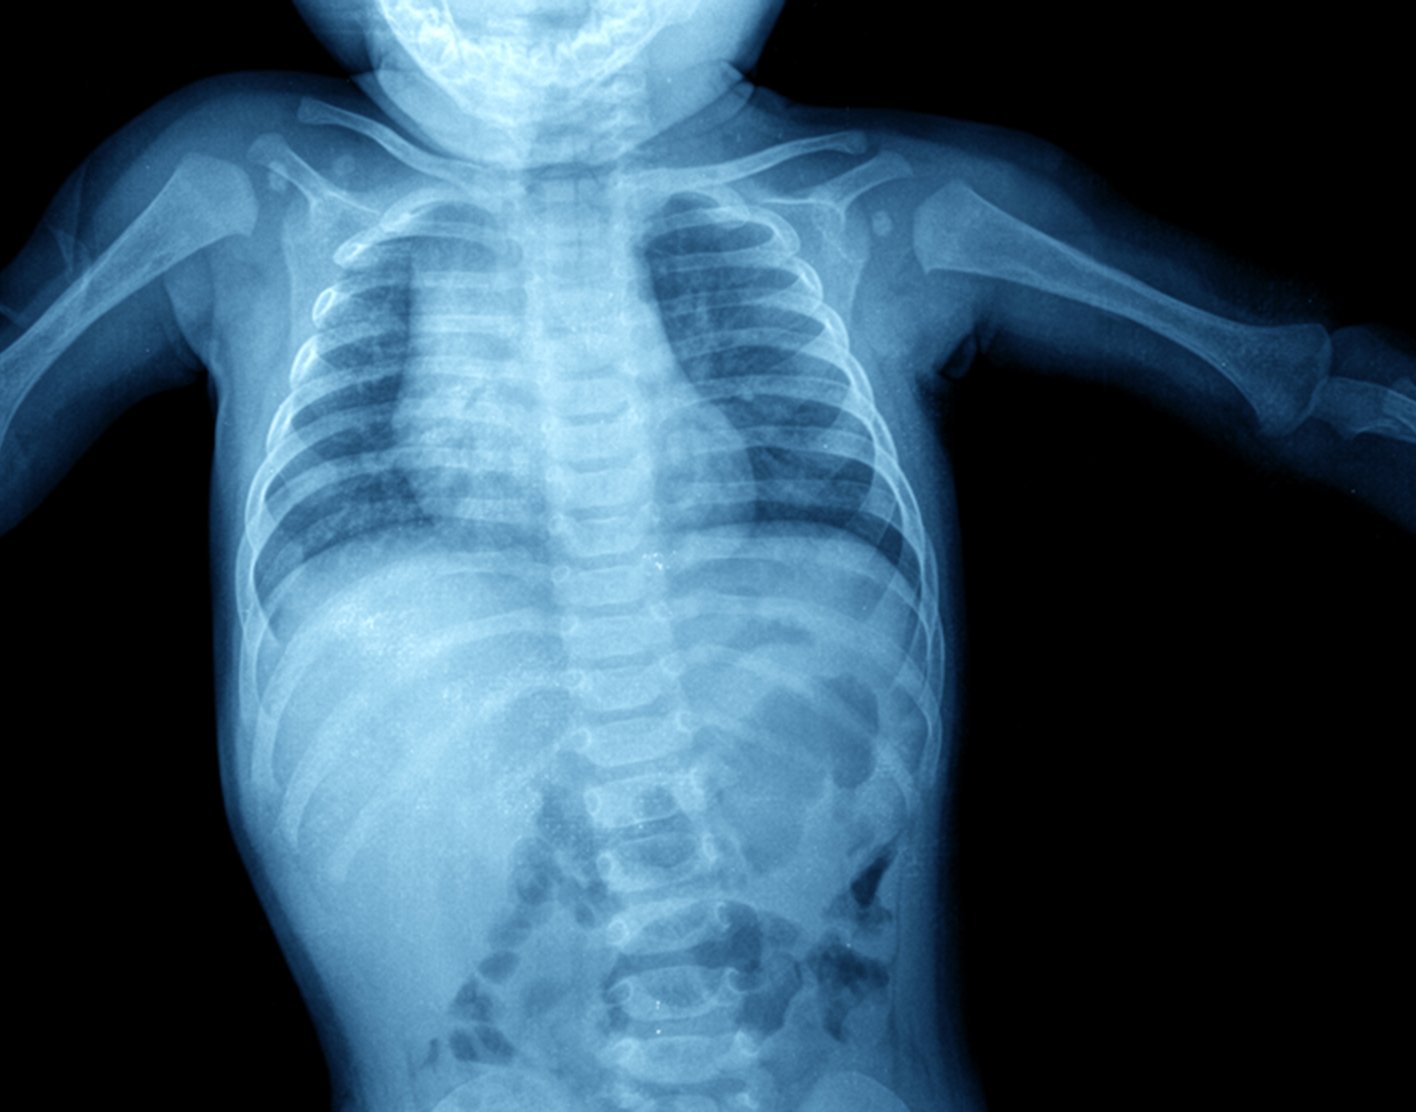

Abdominal x-ray

An abdominal x-ray is an imaging test to look at organs and structures in the abdomen. Organs include the liver, spleen, stomach, and intestines.

When the test is done to look at the bladder and kidney structures, it is called a KUB (kidneys, ureters, bladder) x-ray.